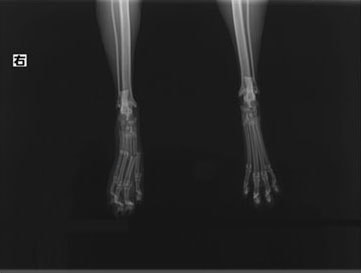

症例3:キルシュナーワイヤーのピンニングによる整復

ペルシャ猫 11ヶ月齢 雄

他院にて左大腿骨遠位の成長板骨折(salter-harrisⅠ型)が認められており、治療相談を目的として来院。当院にて、キルシュナーワイヤーを用いたピンニングにより骨折部位の整復を行いました。術後の経過は良好で、現在も経過観察中です。

術前レントゲン

術後レントゲン

Arthrex社のターゲティングデバイスを用いてピンニングの位置を調整することで、確実な固定を行っています。当院ではこの手術器具以外にも、人の手術にも使用される様々な器具を導入し、手術精度を高め、また医療メーカーと新しい器具の開発、試作にも取り組んでおります。